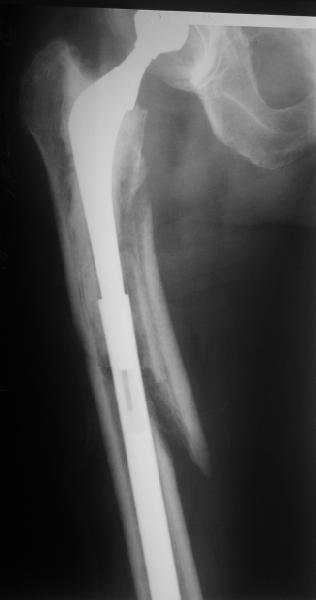

Спасибо за обсуждение. После нескольких дней тракции аппаратом сделали. Попытка закрытой репозиции не удалась из-за смещения по ширине, мешали фрагменты цемента. После их удаления репозиция получилась. Еще убрали немного цемента с ножки по латерльной стороне, чтобы обнажить 40-50 мм ее дистальной части, для плотной посадки гвоздя. Дальнейшее введение гвоздя было несложным. Протез показался нам стабильным в проксимальной части как латерально, так и медиально. Картинки в приложении.

THX for the discussion. After few days of traction by ex-fix the surgery was performed. An attempt of closed nailing was unsuccesful because of fragment translation, which was blocked by cement fragments. After removal of broken cement pieces reduction was reached "automagically". Also some cement from lateral part was removed by

chisel to expose distal 40-50 mm of the stem to allow tight fit of the nail. Further fixation by the nail was pretty easy and straightforward. Images attached. The stem looked stable in its proximal part both laterally and medially. Comments/critics are welcome.

You transformed a cemented hip prosthesis to a cementless revision hip prosthesis with a little approach.